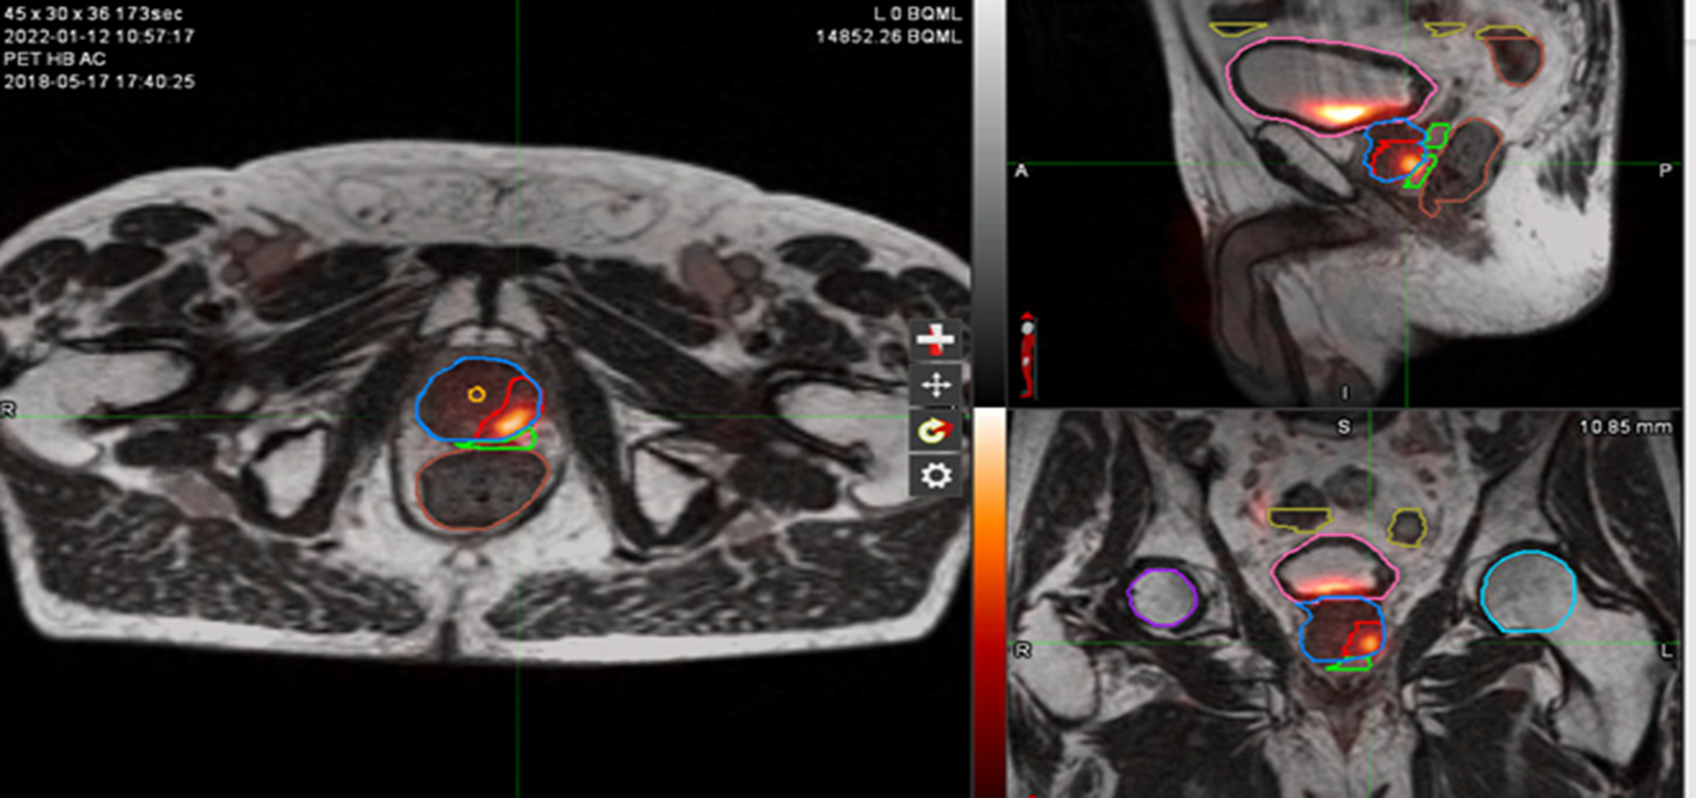

Figure 1: MR and PSMA PET fusion showing recurrence

Figure 2: Contouring target lesion